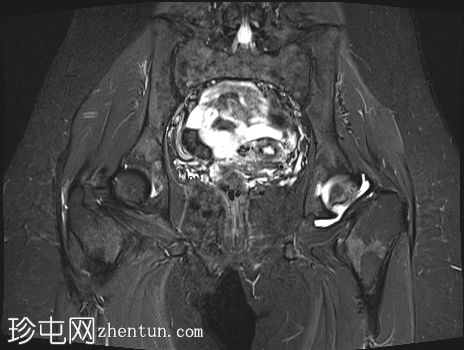

2.jpg

冠状位

T1加权像

左侧股骨头:

T1和T2加权像上可见股骨头前上缘呈蛇形低信号,勾勒出一个地理区域,STIR序列上可见邻近骨髓水肿。

软骨下骨折/新月征,关节面局灶性凹陷——符合软骨下塌陷。

关节间隙中央保持完整,但股骨头轮廓异常,系塌陷所致。

右侧股骨头:

未见骨髓信号异常或软骨下骨折。股骨头轮廓保持完整

关节周围结构:无大量关节积液,无骨关节炎性关节间隙狭窄或边缘骨赘,提示无晚期继发性退行性改变

未发现其他部位急性骨折